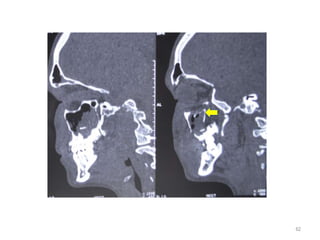

Management

• CT scan coronal , sagittal view

• Diagnosis mainly by clinical examination

• Mostly not require surgical intervention

• Observed for 5-10 days for swelling to

subsides

• Oral steroids (for 7 days) decrease edema

• Pediatric patients with IR muscle trapping

beneath trapdoor fracture - eye movement

aggravate occulocardiac reflex(pain , nausea

and bradycardia)